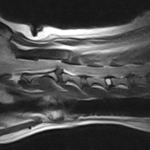

Ventral Slot 高齢のシーズーちゃん。緊急でのC2~C3のVentral Slot、しばらくは呼吸のモニタリングが必要です。 症例カテゴリー 放射線治療整形外科軟部組織外科脳神経外科内科腫瘍外科救急・集中治療リハビリテーション科腫瘍内科内視鏡科脳神経科呼吸器外科中医・漢方猫の腎移植循環器科